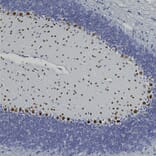

Immunohistochemistry analysis of a formalin fixed paraffin embedded mouse cerebellum section with Anti-FOX2 Antibody (A104328) at a dilution of 1:2,000 detected in DAB (brown) following the ABC method. Counterstained with Hematoxylin (blue). Anti-FOX2 Antibody (A104328) recognizes a nuclear protein found in Purkinje cells and some cells in the granular layer. Interestingly these cells are completely negative for the closely related protein FOX3, also known as NeuN. However FOX3/NeuN is heavily expressed in cerebellar granule cells which do not express FOX2.